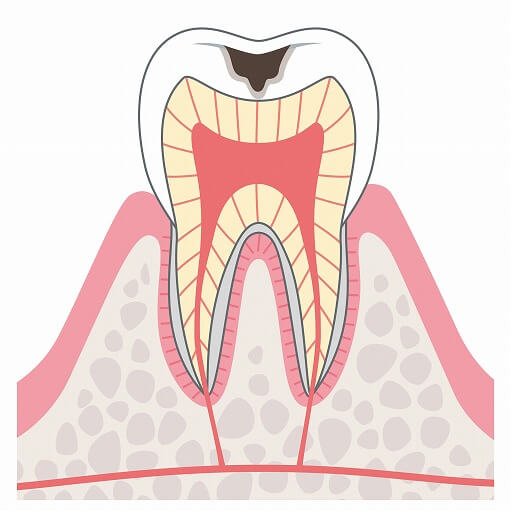

C1

C1は初期状態のむし歯で、歯の表面のエナメル質に少し穴が空いた状態です。むし歯部分が黒、茶色く見えることもありますがこの状態では痛みや症状もないため、むし歯とは気づかないことが多いです。

C1は初期状態のむし歯で、歯の表面のエナメル質に少し穴が空いた状態です。むし歯部分が黒、茶色く見えることもありますがこの状態では痛みや症状もないため、むし歯とは気づかないことが多いです。